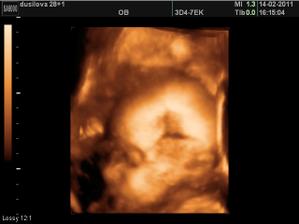

Ve 28tt nám paní doktorka na 3D ukázala krásnýho chlapečka i s jeho pýchou 🙂 Na 99,9% čekáme chlapečka - Tadeáška. Jsem hrozně moc šťastná, že nám vyšlo to co jsme od začátku chtěli - mít starší dcerku a mladšího syna! Tak teď už to jen zdárně doklepat do konce 😀